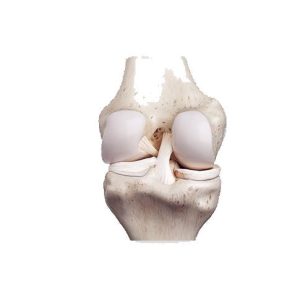

Хиймэл үе солих мэс засал (түнхний үе, өвдөг, мөрний үе 4,328 тохиолдол /мэс заслын хугацаа 1-2 цаг /эмнэлэгт 7-8 өдөр)

Төрөл бүрийн эмгэгээр үений гэмтэл авсан өвчтөнд хамгийн тохирсон хиймэл үе солих мэс засал.

Үений дурангийн мэс засал өвдөг, мөрний үе гэх мэт төрөл бүрийн үений эмгэг 5,251 тохиолдол /мэс заслын хугацаа 1-2 цаг /эмнэлэгт 3-4 өдөр

Үений доторх гэмтсэн хэсгийг үений дурангаар хамгийн бага сорвитойгоор гүйцэтгэж хамгийн эхний нөхөн сэргэх зорилготой мэргэжилийн мэс ажилбар.